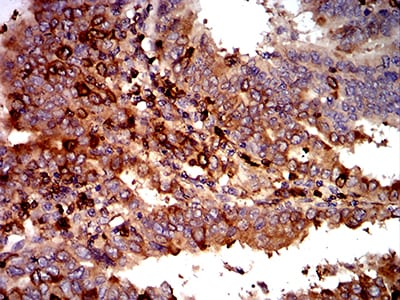

- Immunohistochemical analysis of paraffin-embedded human ovarian cancer tissues using C3C mouse mAb with DAB staining.

- Immunohistochemical analysis of paraffin-embedded human endometrial cancer tissues using C3C mouse mAb with DAB staining.